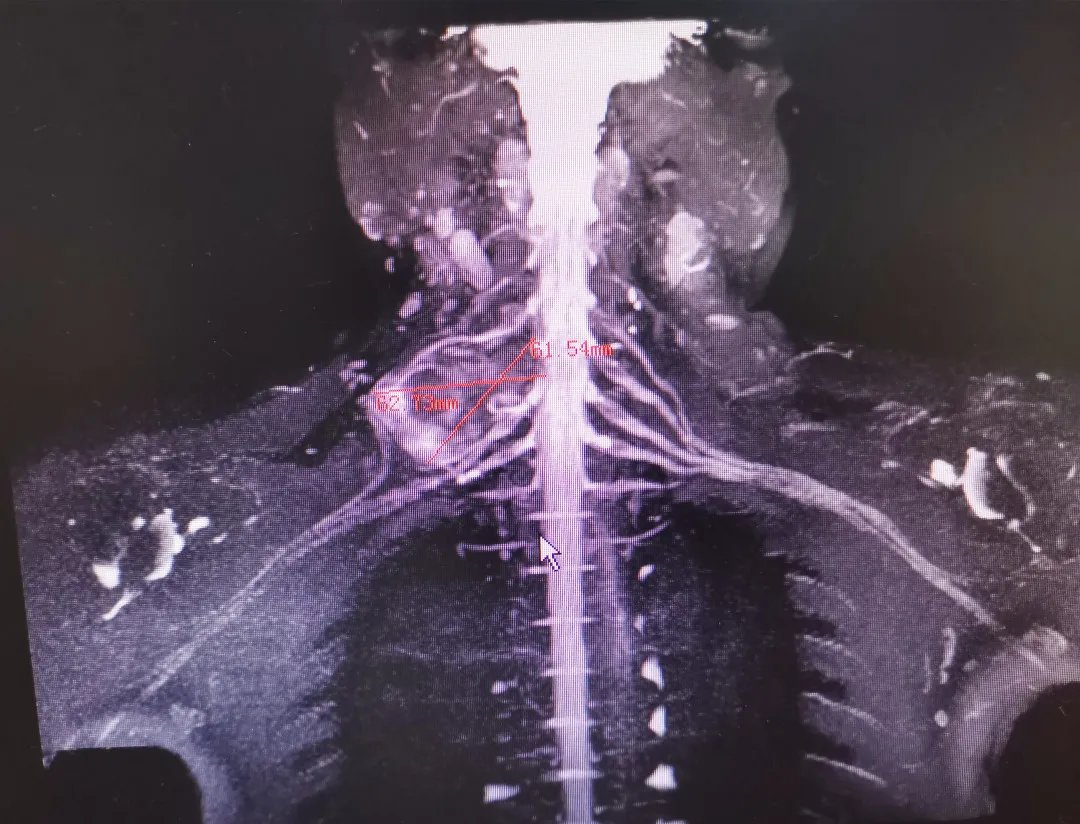

文章插图

术前头颈部CTA显示:肿瘤压迫椎动脉

【 多学科|38岁男子脖子上长鹅蛋大肿块,医生多学科联合切除巨大神经鞘瘤】头颈部增强MRI显示:肿瘤约为6.1×6.2cm大小

进一步检查发现,肿瘤约6.1×6.2cm大小,已经严重压迫椎动脉及周围神经,并向椎管内生长,导致椎间盘左后方突出,椎体骨质破坏,有脊髓损伤、高位截瘫的风险。既要保证肿瘤完整切除,又不能损伤周围重要血管和神经,手术难度和风险不言而喻。